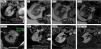

Por su baja densidad vascular, el realce es menor que en otras neoplasias renales, lo que facilita su caracterización. En tomografía computarizada puede no realzar de manera concluyente, y entonces es indistinguible de un quiste hiperatenuante. La ecografía con contraste y la resonancia magnética son más sensibles para detectar vascularización. Son además característicos un patrón vascular específico, hipointensidad en T2, restricción de la difusión del agua y aumento de señal en fase opuesta.

Due to their low vascular density, papillary renal cell carcinomas enhance less than other renal tumors, and this facilitates their characterization. On computed tomography, they might not enhance conclusively, and in these cases they are impossible to distinguish from hyperattenuating cysts. Contrast-enhanced ultrasonography and magnetic resonance imaging are more sensitive for detecting vascularization. Other characteristics include a specific vascular pattern, hypointensity on T2-weighted images, restricted water diffusion, and increased signal intensity in opposed phase images.